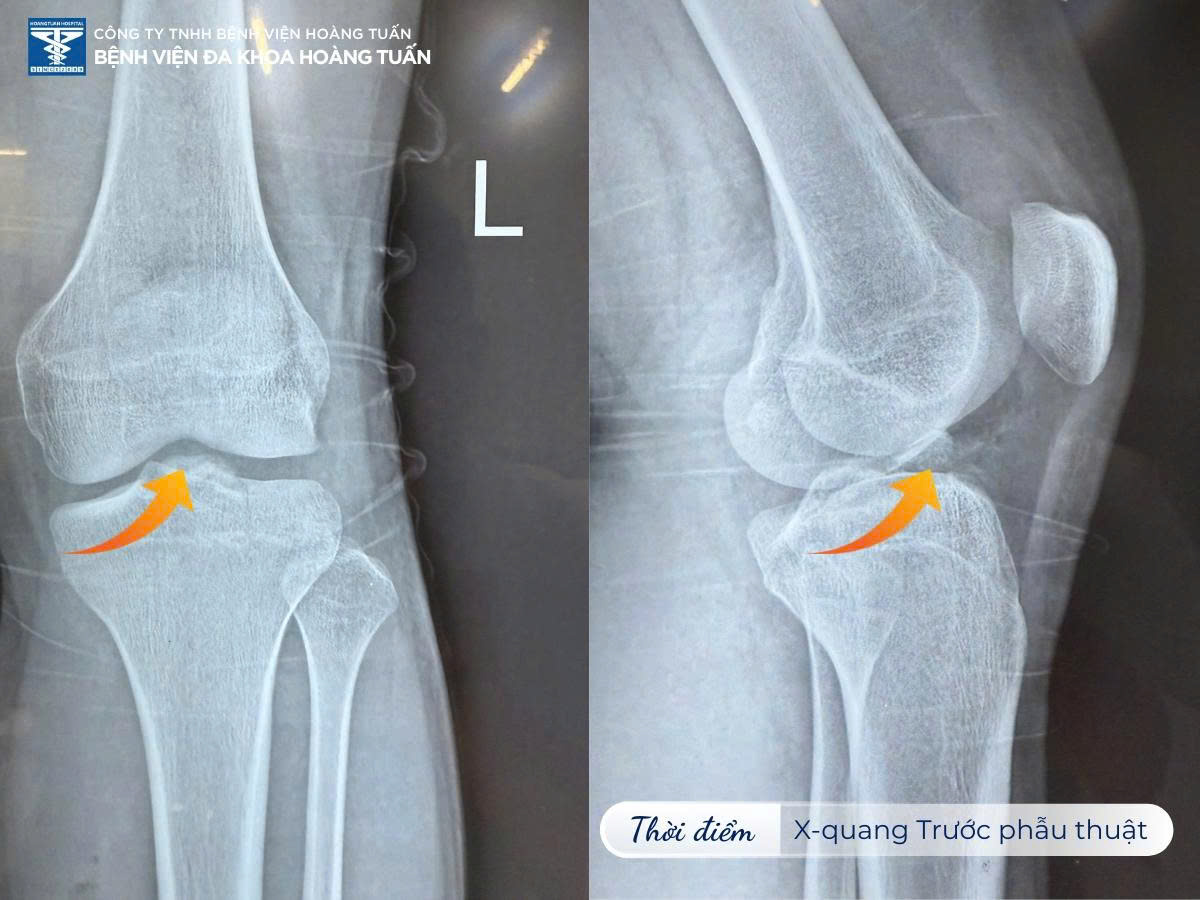

Vào thời điểm cuối tháng 09/2025, Bệnh viện Đa khoa Hoàng Tuấn tiếp nhận một trường hợp bệnh nhân V.V.T.Đ nam 17 tuổi đến khám trong tình trạng đau khớp gối trái khoảng 01 tuần, được tuyến cơ sở y tế trước đó cố định bằng bột ống với chẩn đoán gãy mâm chày trái.

Qua thăm khám, nhận định tình trạng bệnh và chỉ định chụp X-quang kiểm tra. BSCKI. Vũ Quốc Dũng – Khoa Ngoại CTCH Bệnh viện Đa khoa Hoàng Tuấn ghi nhận bệnh nhân có biểu hiện bong điểm bám dây chằng chéo trước vùng gối trái. Bệnh nhân được tư vấn thực hiện phương pháp phẫu thuật đính điểm bám dây chằng gối trái bằng dụng cụ chuyên sâu. Đây cũng là phương pháp tối ưu nhất nhằm đưa các tổn thương về tình trạng giải phẫu ban đầu, tránh các biến chứng do bất động lâu và nguy cơ thoái hóa dây chằng khớp gối.